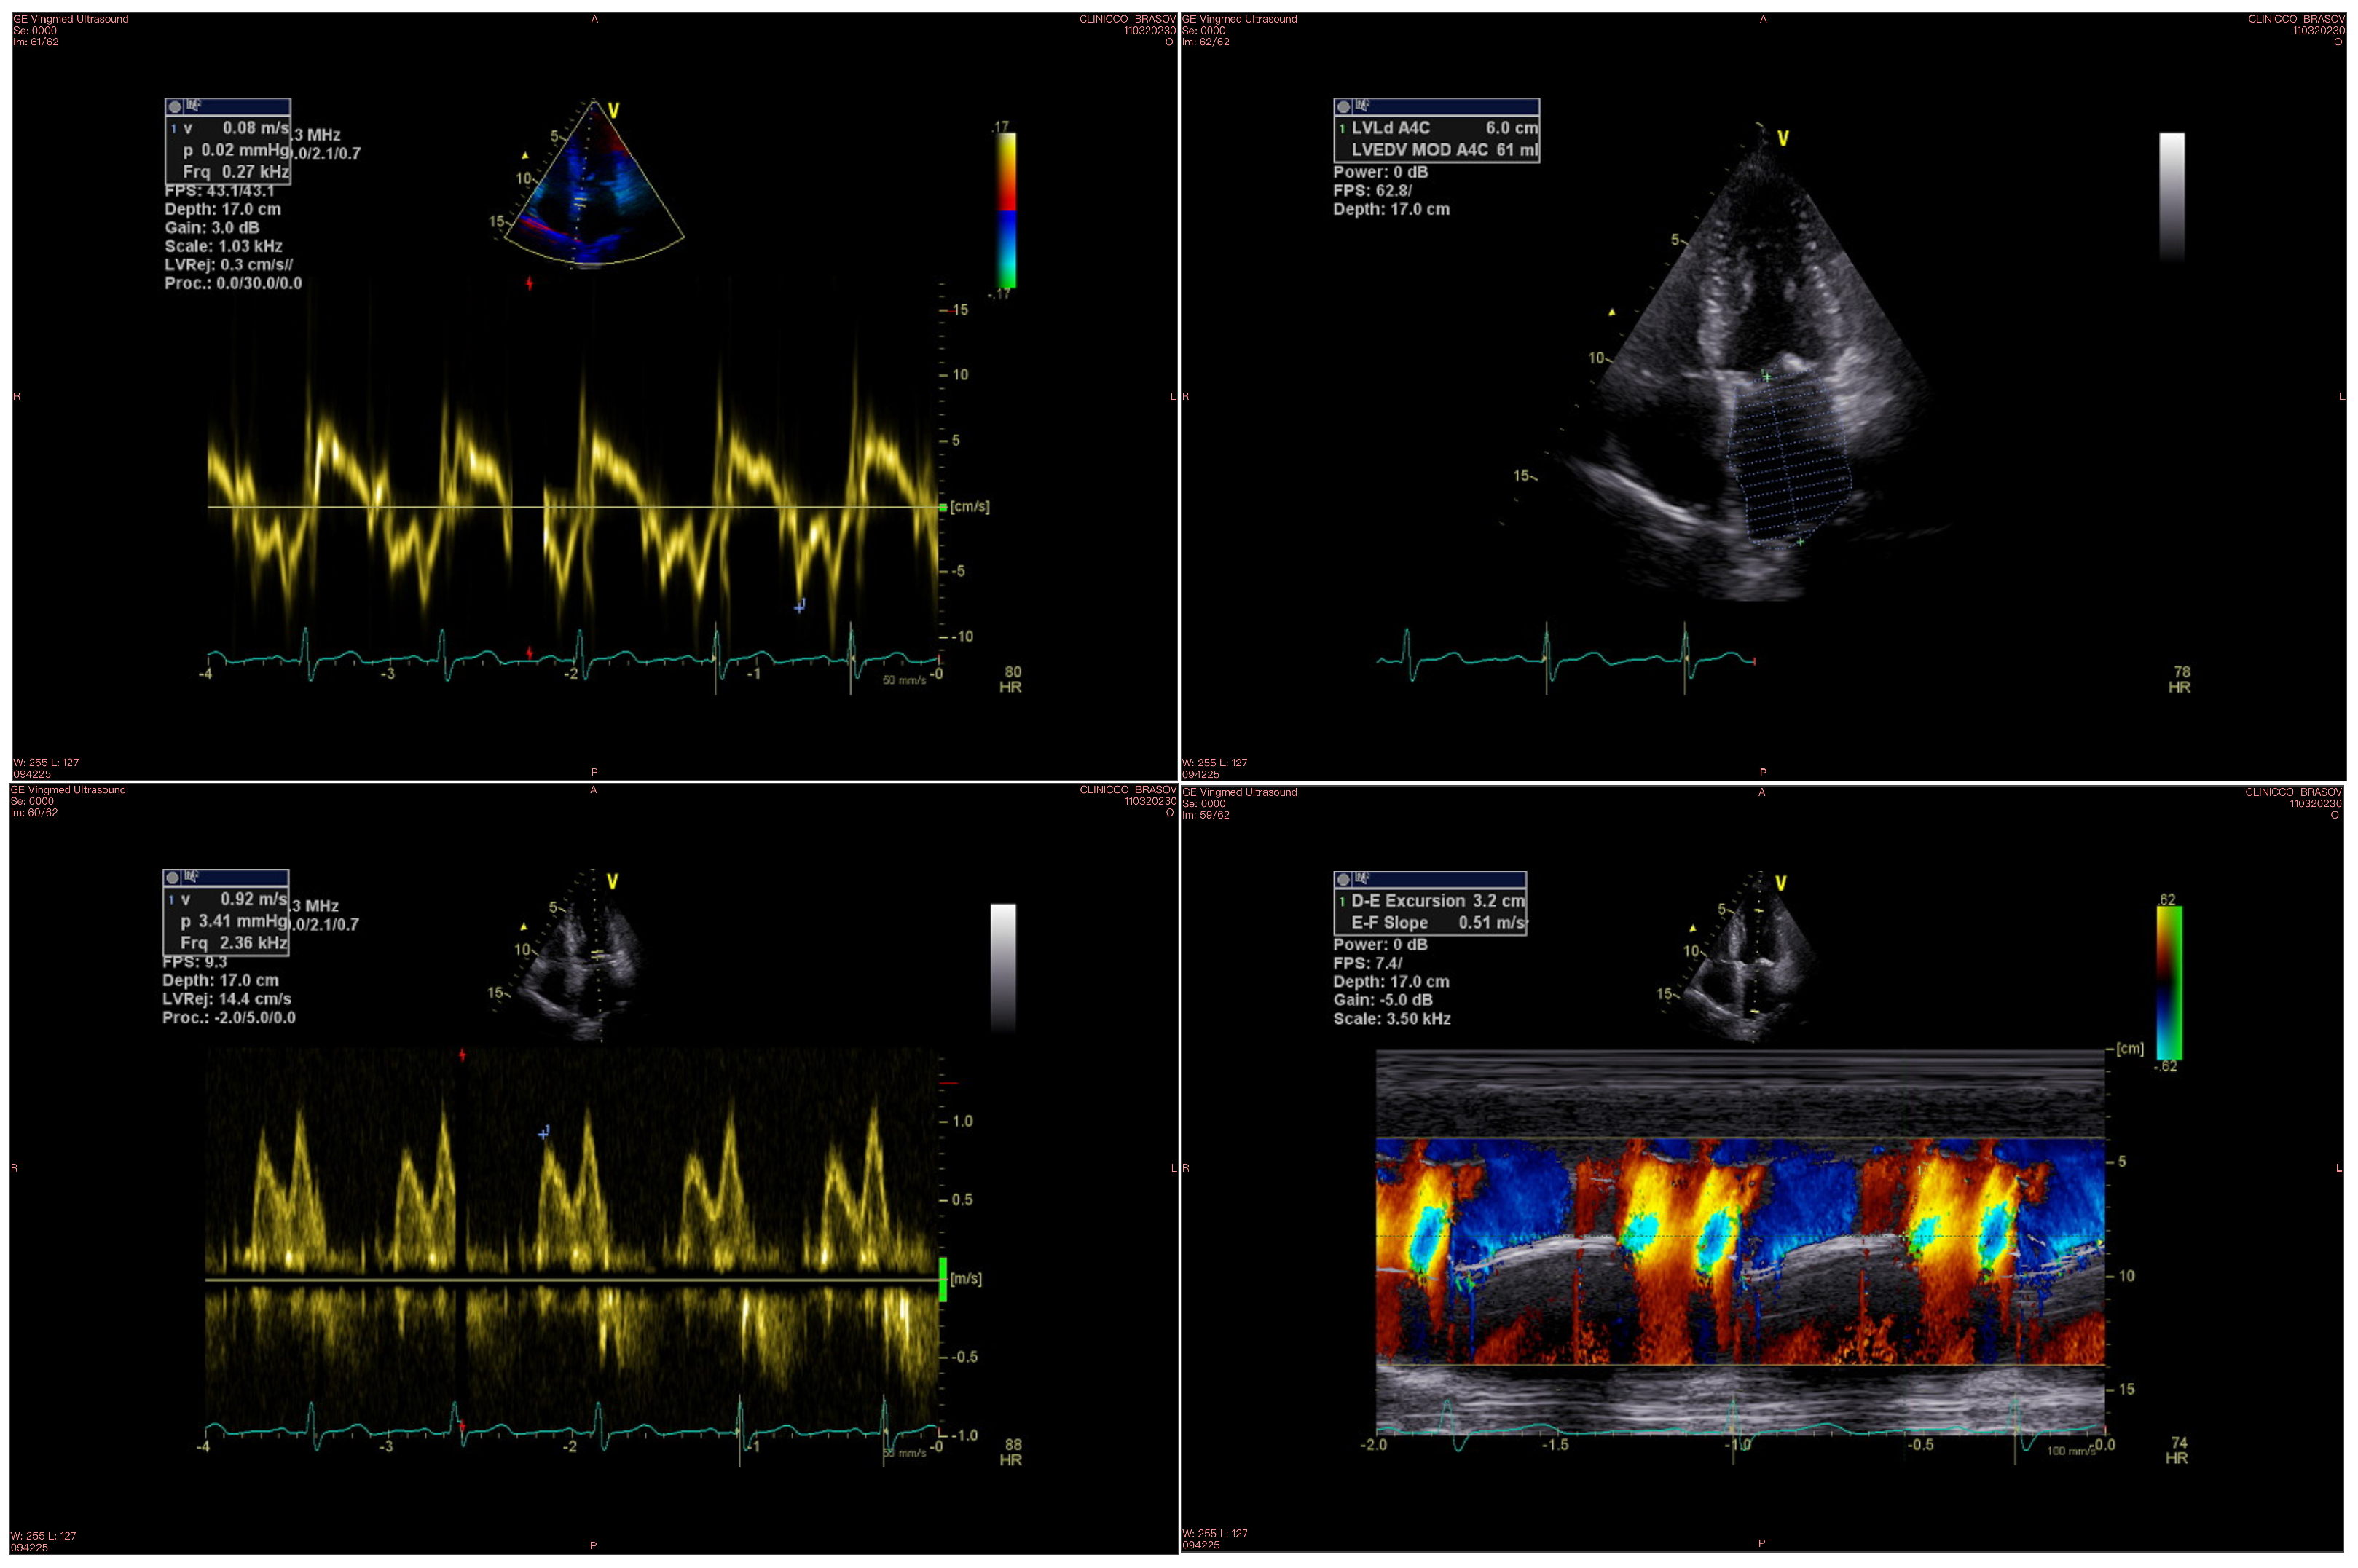

An example of echocardiographic parameters used for evaluating diastolic function is displayed in Figure 1.

Figure 1.

Diastolic function parameters measured by echocardiography: the upper left image shows the Em wave, the upper right image shows the LA volume, the bottom left image shows the E wave, and the bottom right image shows the Vp measurement.